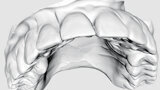

Navigovaný endodontický přístup u kalcifikovaných frontálních zubů: Kazuistika